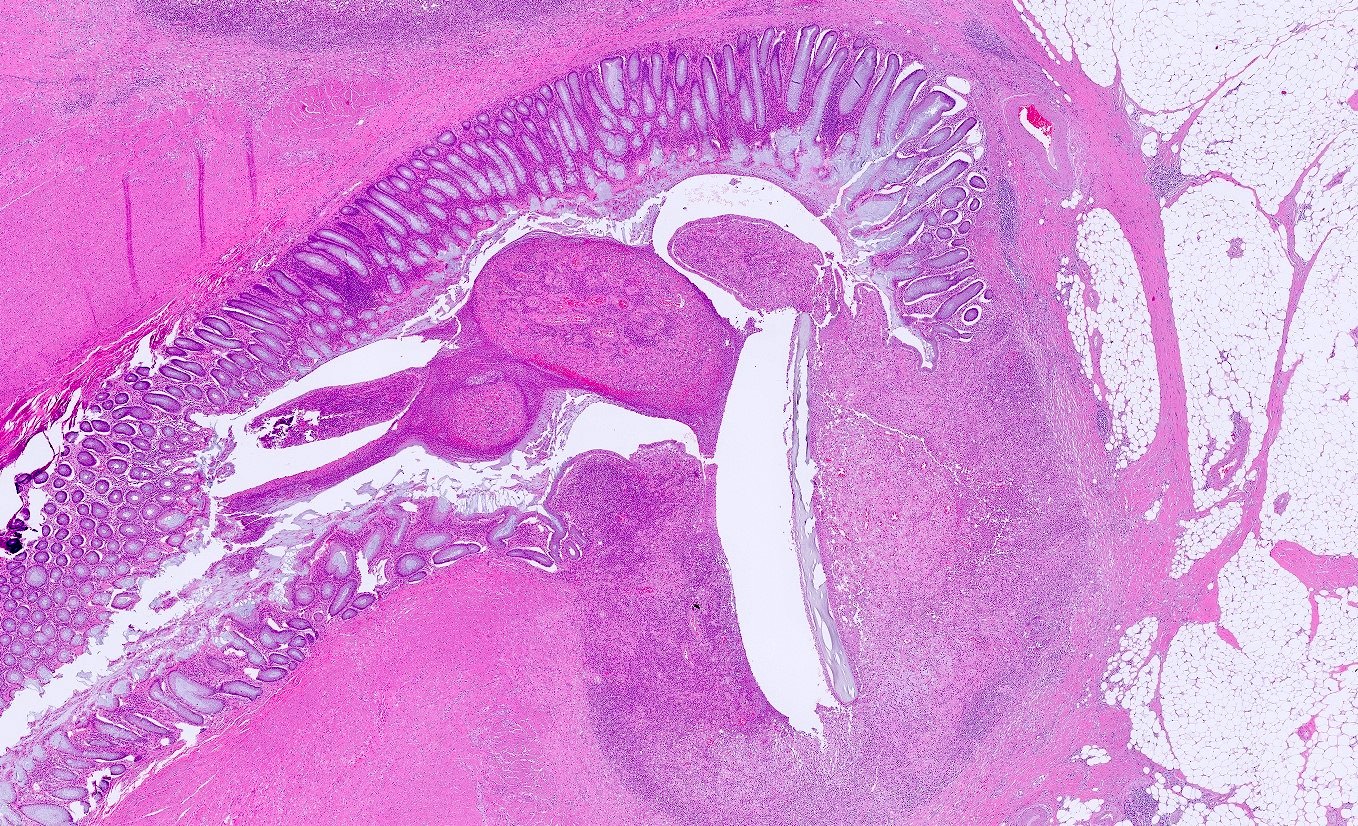

Microscopic (histologic) description

- Mucosa may be normal to markedly abnormal

- Expansion of lamina propria by lymphoplasmacytic infiltrate (more prominent in basal half)

- Lymphoglandular complexes, mucin depletion, focal Paneth cell metaplasia (in chronic cases) may be seen (J Clin Gastroenterol 2004;38:S11)

- Muscularis mucosa extends towards surface between elongated crypts

- Shortening of the affected bowel and hypertrophy of circular muscle layer (myochosis) leads to exaggerated mucosal folds (Am J Surg Pathol 1991;15:871)

- Some cases can show lamina propria fibrosis, crypt elongation on the tips of prominent mucosal folds, like mucosal prolapse syndrome in rectum and anus (J Clin Gastroenterol 2008;42:1137)

- Hemosiderin deposition in submucosa may be seen (StatPearls: Diverticulosis [Accessed 21 April 2022])

- Can mimic inflammatory bowel disease

- Hyperplasia of lymphoid aggregates is one of the earliest signs of diverticulitis

- Cryptitis, crypt abscesses, peridiverticular abscess and fistulas may be superimposed on this background in acute diverticulitis

- Tracking abscesses can spread longitudinally or circumferentially and can cause diverticular colitis

- Persistent localized inflammation can lead to phlegmon which is a thickened, firm segment of bowel wall that can lead to strictures and acute or subacute large bowel obstruction (Best Pract Res Clin Gastroenterol 2002;16:543)

Microscopic (histologic) images

Contributed by Bindu Challa, M.D. and Martha M. Yearsley, M.D.